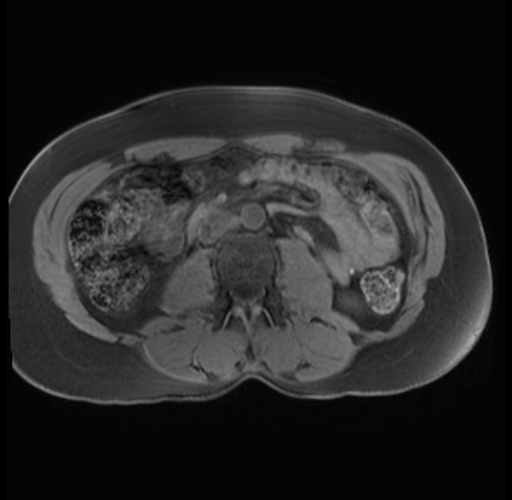

Imaging Analysis

Look through the patient's CT scan to identify any areas of concern for the necessary procedure.

Based on your CT findings, which issue(s) are present and would give reason for "planned slowing down moment(s)" in this case?

Considering a standard distal pancreatectomy procedure, what step(s) of the operation would you do differently in this case?